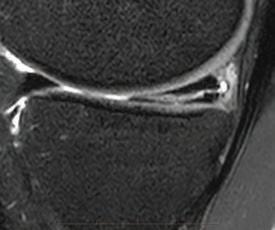

the line? Dr David Colvin 52 Imaging of the knee Dr Gavin Watson 55 Shoulder instability surgery: do it right, do it once Dr William Blakeney 61 A new health paradigm Dr